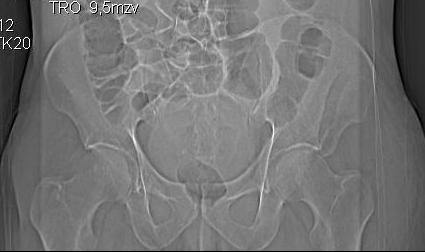

Уважаемые коллеги! Хотелось бы услышать ваше мнение. Мужчина 50л поступил с переломами костей таза. Закрытый перелом крыла подвздошной кости, переднего края вертлужной впадины справа.

Достаточно ли консервативного лечения, стоит ли беспокоиться о переднем крае? В приложении КТ.

По предоставленым снимкам верифицировать повреждение невозможно.

Покажите обзорный снимок таза и проекции Judet.

Если уж делали КТ, то наверное сохранились сами срезы.